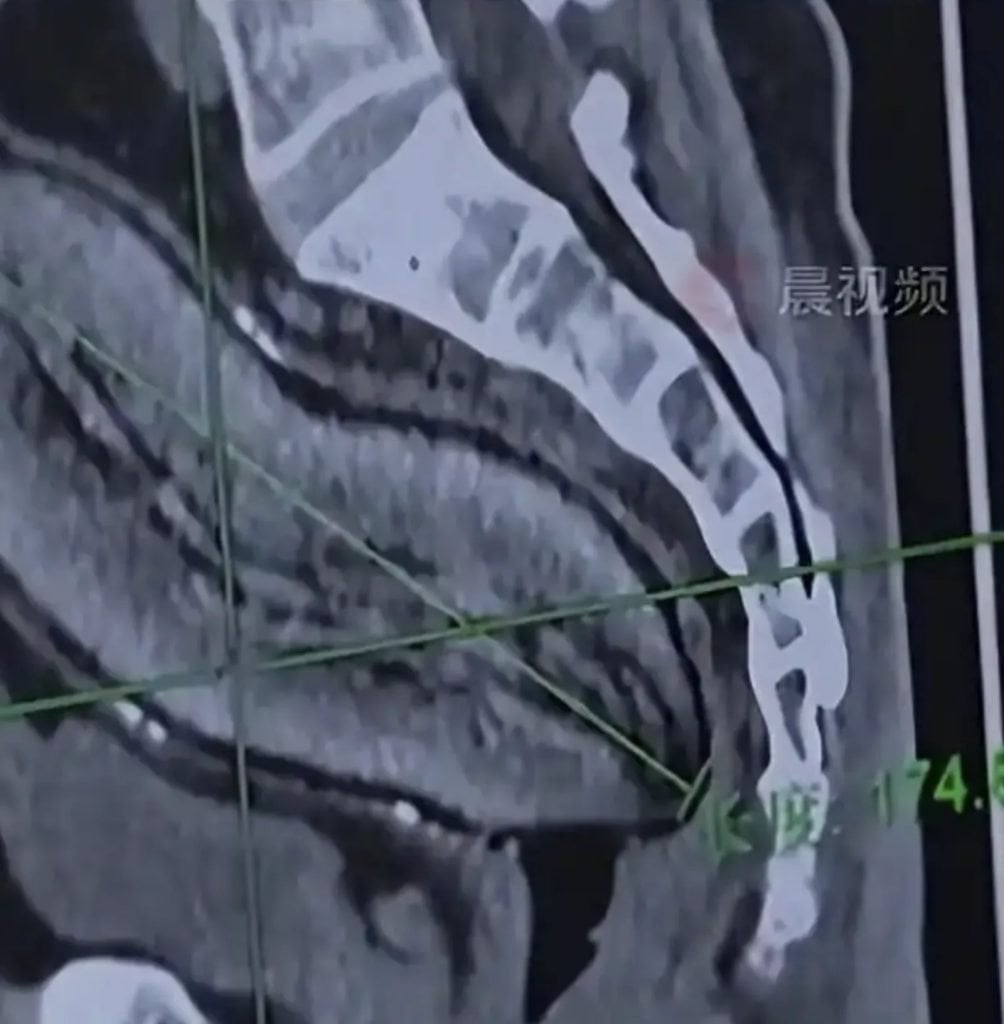

Батат у тілі чоловіка / © Jam Press

Заступник директора відділення проктології та дерматології лікарні доктор Сю Гуолінь повідомив, що предмет мав приблизно 17 см у довжину та майже 7 см у ширину.